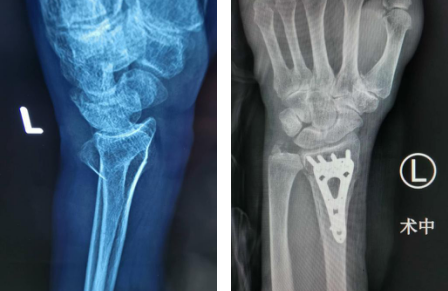

接诊的是手外腕关节病专家齐伟亚主任。齐主任问道:“老太太,手腕怎么受伤的啊?”刘老太将前因后果一一告诉了齐主任。齐主任为刘老太做了专业的检查,检查结果显示刘老太左腕桡骨远端骨折。齐主任向她介绍了桡骨远端骨折的治疗方案,有传统治疗,也有手术治疗,刘老太一听果断选择了腕关节镜微创术。

刘老太身体素质不错,没有什么基础病,万幸摔倒后腰部没有受伤,所以刘老太的家人当即同意手术方案。当天下午,齐主任为刘老太做了微创术,在关节镜辅助下,进行了切开、复位、内固定等操作,1个多小时就完成了手术。

术前(左)术中(右)